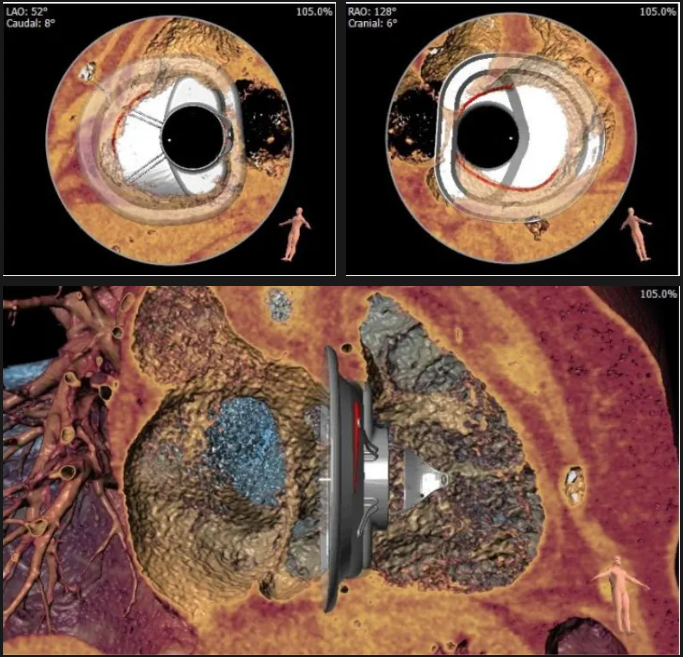

術前心臟CT評估

三尖瓣環平均周長徑54.3mm,最大直徑57mm

心房側周長平均徑(封堵高度)74.0mm

三尖瓣環切線位夾角 103°

術中經食道超聲輔助下可見LuX-Valve Plus夾持件抓捕瓣葉狀態良好,夾持件在位,室間隔錨定位置良好,假體瓣膜整體錨定狀態穩固。

術后即刻經食道超聲可見,三尖瓣假體瓣膜位置合適,牛心包瓣葉運動狀態良好,開閉正常,瓣周及瓣葉對合緣處未見明顯返流,心電圖及心包狀態較術前無明顯變化。